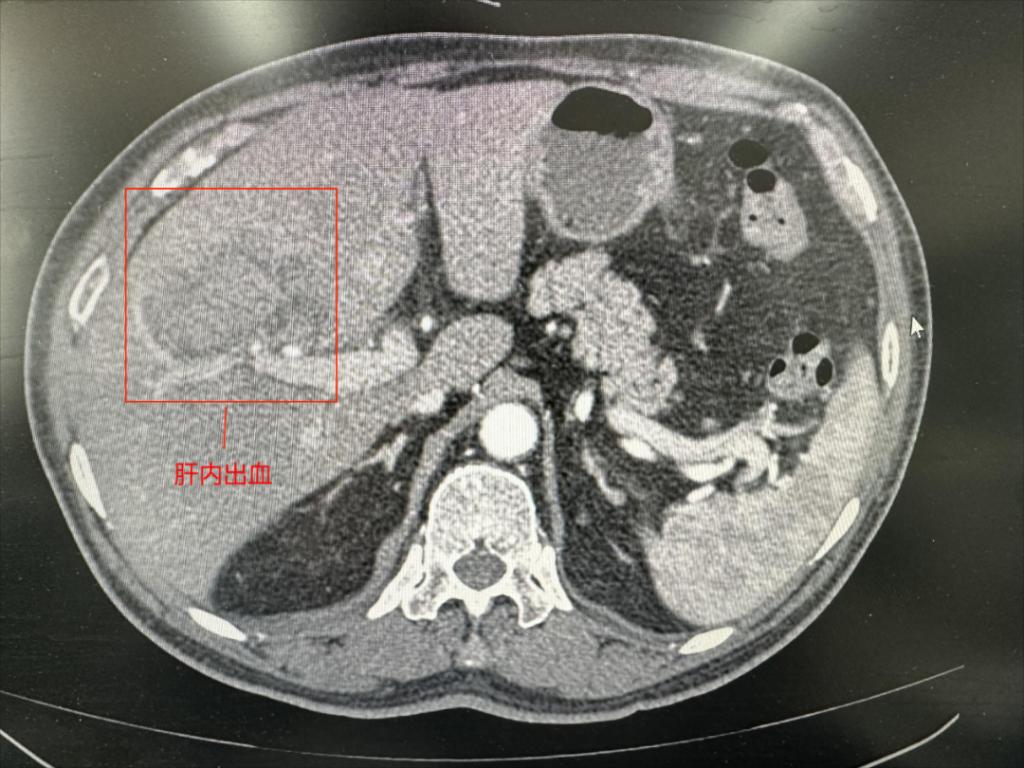

2023年11月2日,64岁的薛先生突发意识丧失,晕倒后伤及右上腹部,由路人拨打120就诊于我院急诊,自述感右上腹剧烈疼痛。立即行CT检查提示:肝右叶挫裂伤、肝内血肿表现。初步诊断为肝脏破裂出血。医院开通紧急救治绿色通道,紧急启动多学科联合会诊。患者系多发伤,病情危重,肝挫裂伤若在全麻下行开腹手术,手术风险极大,即使手术取得成功,也可能会在后期康复过程中面临多种并发症。经我院会诊专家再三讨论,最终决定行介入手术治疗。

肝脏创伤破裂诊断依据:①病史及体征,患者多有右胸背部、右中上腹部受伤史,肝区叩击痛、血性腹膜炎体征及腹穿抽出不凝血等;②辅助检查,近年来,B超及CT作为一种有效、迅速的诊断和鉴别肝创伤的手段,得到了广泛的接受和应用,文献报道B超检查阳性率为95.5%;CT检查阳性率为100%。B超及CT检查可评估肝损伤的范围、深度、部位及失血量,对指导临床治疗的方法极有价值。但当肝门区血管或胆管损伤,单纯按照B超及CT分级并决定是否手术治疗比较困难,可结合临床具体分析。